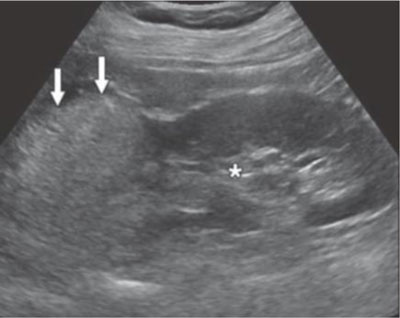

Figure 1

US image showing a fat-rich AML (arrow). The tumour is more hyperechoic than the right renal sinus (asterisk) [10].